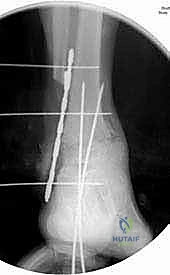

5. إدخال وتثبيت الصفيحة النصلية (Blade Plate)

هنا تكمن المهارة الجراحية الفائقة. يتم تشكيل مجرى دقيق داخل عظمة الكعب باستخدام إزميل خاص، ثم يتم طرق "نصل" الصفيحة المعدنية بحذر شديد داخل عظمة الكعب لضمان أقصى درجات الثبات.

6. التثبيت النهائي بالبراغي (Screw Fixation)

بعد التأكد من الموضع المثالي للصفيحة والنصل، يتم تثبيت الجزء العلوي من الصفيحة على عظمة قصبة الساق باستخدام براغي قشرية (Cortical Screws) قوية. يتم وضع العظام تحت ضغط ميكانيكي (Compression) لتحفيز الخلايا العظمية على الالتحام السريع.